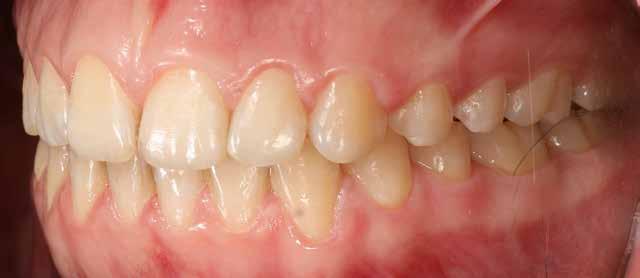

Ebben a cikkben egy 16 éves lánypáciens esetét szeretném bemutatni (1–7. képek)

Mint sok páciensem, akiknél végül nincs szükség állcsontműtétre, ők is megjárták a saját „kálváriájukat”: már több fogszabályozó kollégánál jártak, és mindegyik azt mondta nekik, hogy állcsontműtét nélkül az eset nem megoldható.

Végső elkeseredésükben időpontot foglaltak hozzám, és legnagyobb örömükre egyértelműen látszódott, hogy a Pitts Protokollok-kal nincs szükség az orthognáth műtétes beavatkozásra.